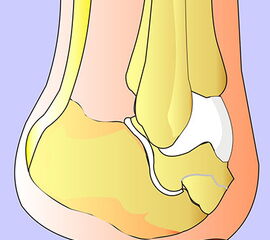

Problematik des nicht antagonisierten Sehnenzugs nach Lisfrancamputation. Die  Fußhebung ist ausgefallen. Durch Zug des M. trizeps surae resultiert eine Spitzfußstellung, die bei Neuropathie ein chronisches Ulkus im Bereich der Hauptbelastungszone hervorr

Abbildung 42

Amputation in der Chopartlinie

Bei der Chopartamputation – (wie auch bei der Amputation in der Bona-Jäger-Linie) – ist zu beachten, dass die Ansätze der Fuß- und Zehenheber entfernt werden, also der Rückfuß durch den Zug des M. triceps surae eine Equinusstellung einnimmt (Abb. 43). Die Folge können hartnäckige Ulzerationen an der Spitze des Stumpfes sein (Abb. 44). Neben der Durchtrennung der Achillessehe (Abb. 45) sollte die plantare, distale Knochenkante abgerundet werden (Abb. 46).